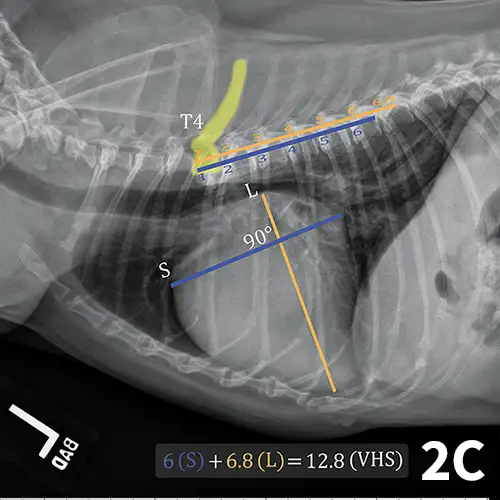

The ACVIM consensus statement on degenerative MVD recommends baseline thoracic radiography for dogs with a new murmur, then annually thereafter.6 For practitioners adhering to these guidelines, annual calculation of VHS and rate of change from previous imaging should become standard practice and may help identify those patients at higher risk of developing CHF in the coming year. Figure 2 illustrates annual radiographs taken in a patient with progressive cardiomegaly.

FIGURE 2A

Progressive cardiomegaly noted on annual evaluations in a dog with MVD.